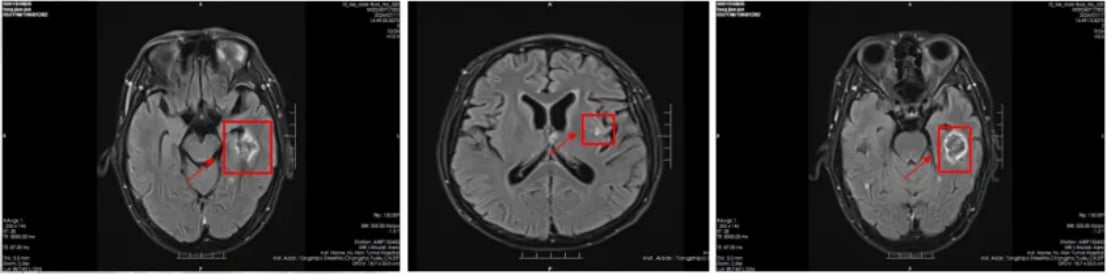

脑部转移灶变化:

治疗前(2024-5-14),头部影像显示脑内多发结节肿块,考虑为转移瘤。经过治疗后(2024-7-17),脑内多发转移瘤较前明显缩小、数量减少,且活性降低,显示出卓越的颅内病灶控制效果。

图3:治疗前头部影像

图4:治疗后头部影像